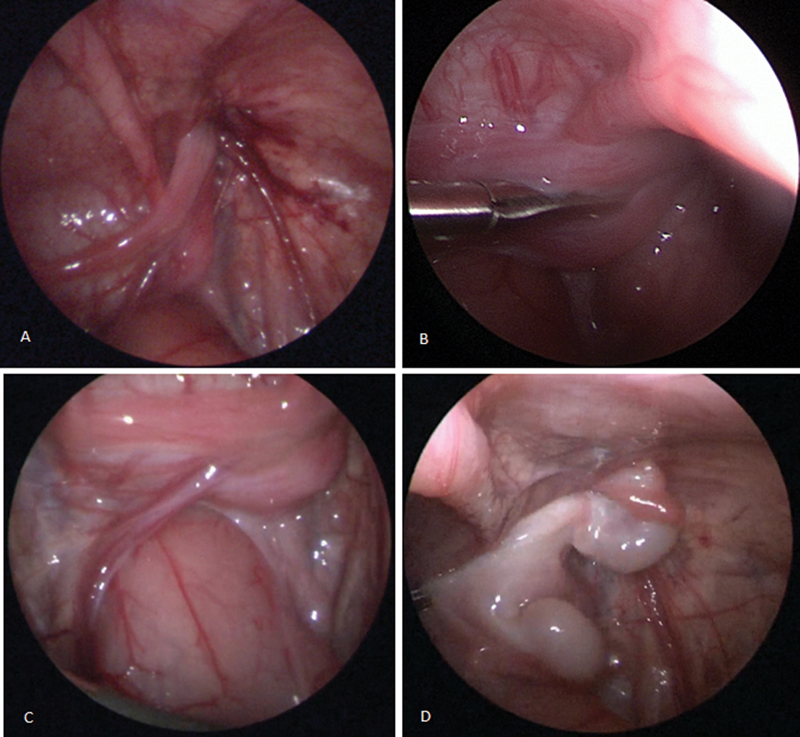

Transverse testicular ectopy (TTE) is a rare anomaly in which both testicles descend through the same inguinal canal. Different variants of this anomaly exist, with the most common presenting as two separate spermatic cords and testicular vessel bundles. The management of this condition is challenging, as various factors have to be considered. We report on a 2-month-old preterm boy with TTE, admitted to the hospital due to an ipsilateral incarcerated inguinal hernia. Diagnostic workup included a physical examination revealing a large swelling in the right groin, ultrasound imaging that showed both testicles located in the right inguinal canal, and laboratory tests indicating a deficiency of anti-Mullerian hormone. All of these findings confirmed the diagnosis of TTE. Surgical treatment included diagnostic laparoscopy with herniorrhaphy, followed by inguinal revision with transseptal orchidopexy in a second procedure. The 12-month follow-up was uneventful. Though rare, TTE is an important differential diagnosis in case of an incarcerated hernia combined with (contralateral) empty scrotum. Pediatric surgeons must be aware of this entity. Meticulous diagnostic workup and careful surgical management are mandatory.